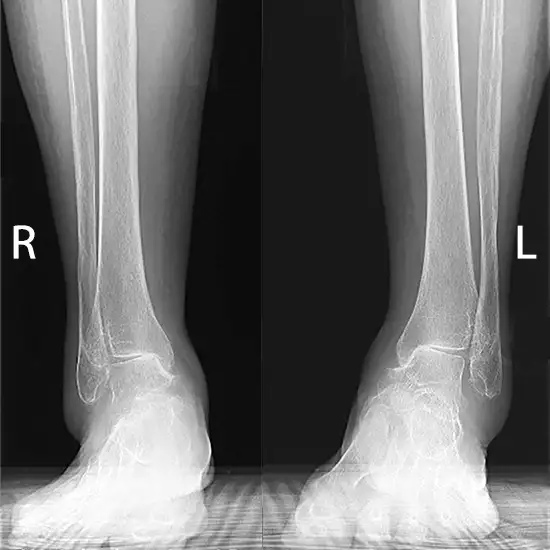

X-Ray Both Ankle AP View

The Anteroposterior (AP) view of both ankles is used to see the bones of the ankle and the skin and muscles around it. An anteroposterior (AP) chest x-ray is performed with the patient's back to the film plate and the x-ray equipment in front of them.

The doctor gives this test to find out if any bones in the ankle joint are broken or fractured and check how the broken bone is healing. It can also tell you whether you have an infection, osteoporosis, a deformity, or if your bones are growing abnormally.